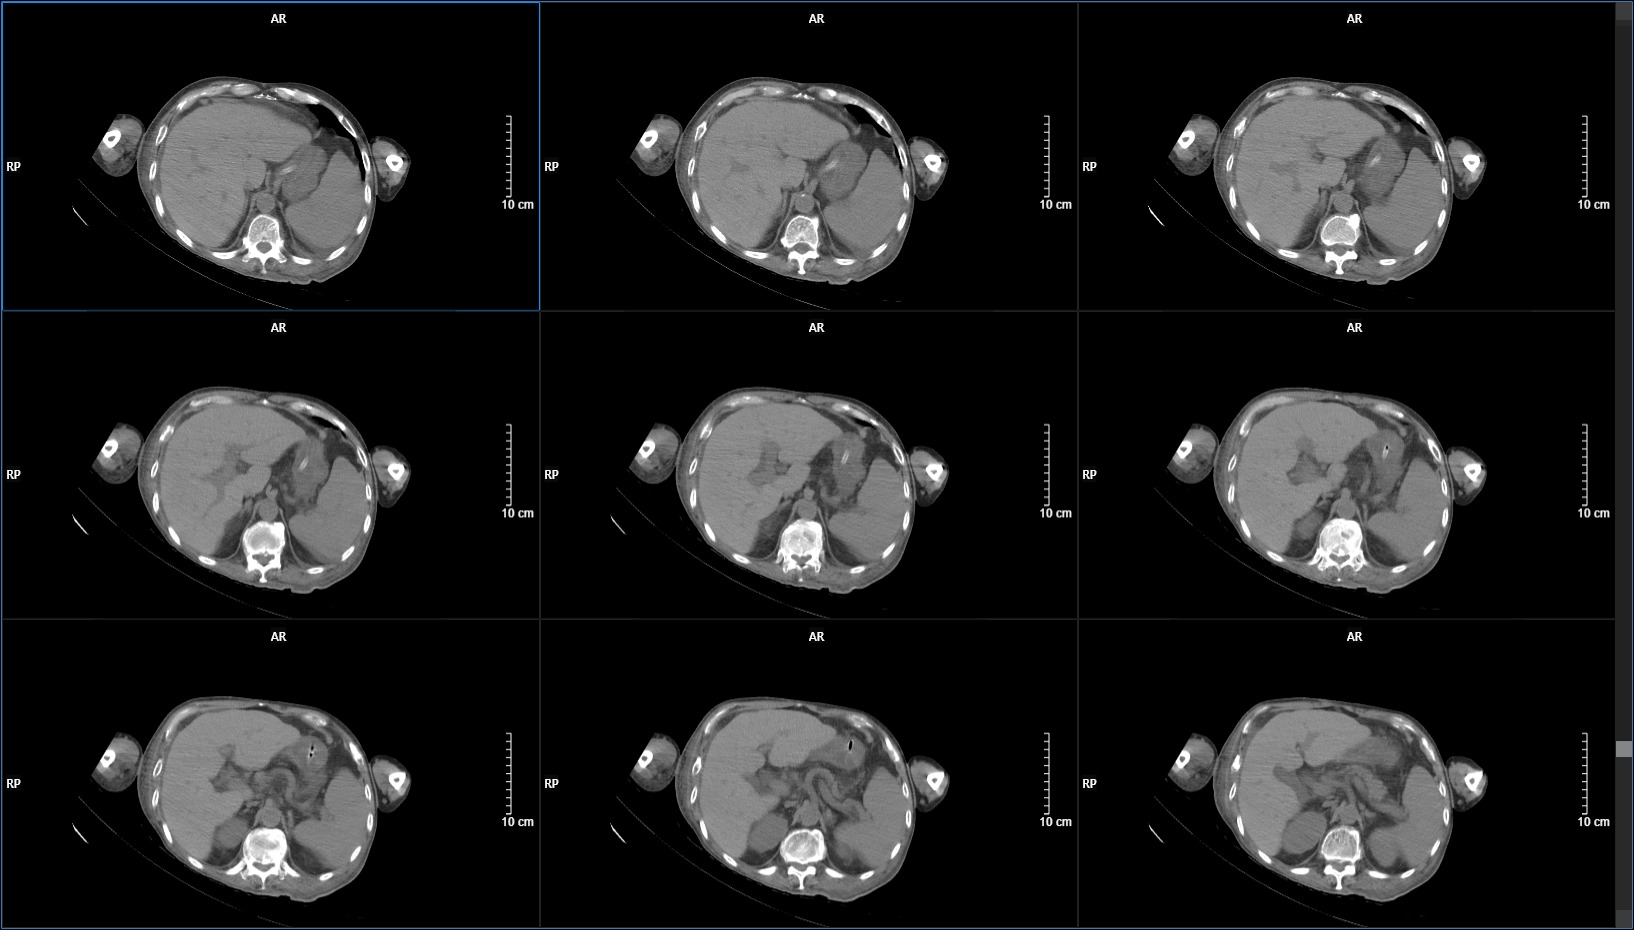

1周后,患者大便呈墨绿色稀便,腹腔出现积液,颅脑复查无变化。伴高热,血感染指标升高明显,但腰穿脑脊液结果正常,腹腔引流液化验结果也无异常。应用万古霉素、利奈唑胺等均效果差。意识也逐渐变差。

考虑腹腔分流管相关导致腹腔感染(仍然疑惑,各项检查数据均正常,无菌性炎症?网膜不吸收原因?),给予腹腔引流+拔除腹腔分流管,未在出现腹腔积液。但意识也回到入院时水平,肺部感染等并发症也逐渐出现。